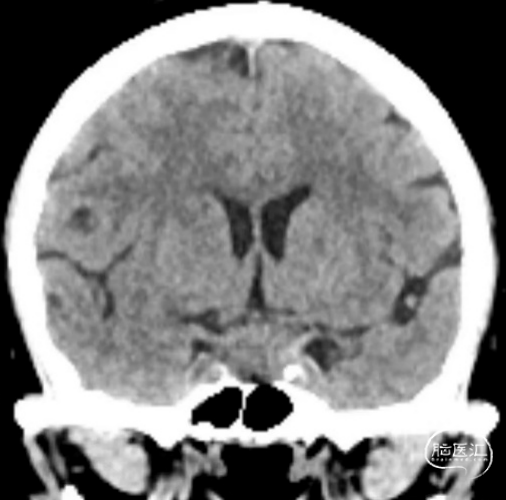

头颅CT:鞍区饱满,蝶鞍等密度占位,未见明显钙化。

头颅增强核磁:蝶鞍可见片条状异常信号影并向前延伸,长度约33mm,高约14mm,垂体显示不清,视交叉受压,增强后强化明显,局部欠均匀,可见脑膜尾征,考虑为脑膜瘤可能。